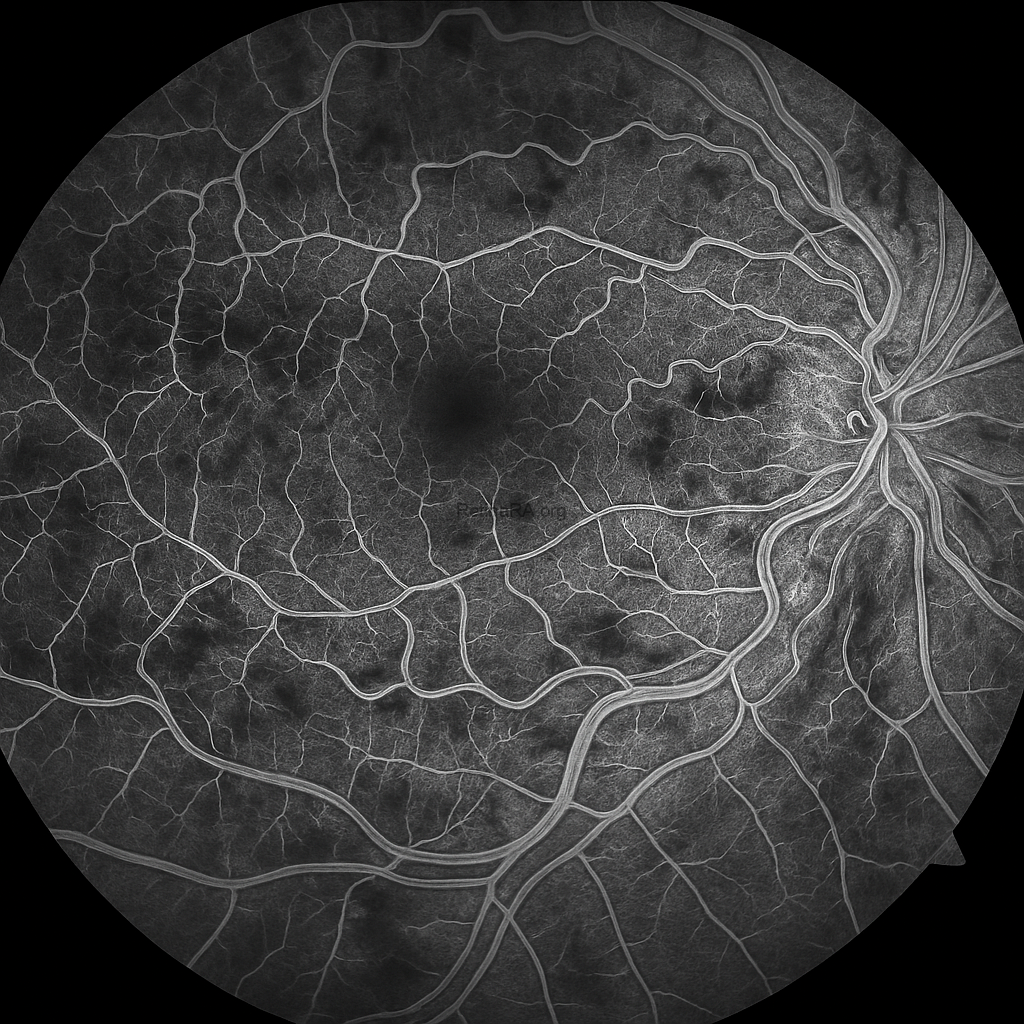

Early Phase

The early phase fluorescein angiography image demonstrates delayed venous filling with irregular and tortuous retinal veins. Areas of hypofluorescence are observed corresponding to blocked fluorescence from widespread intraretinal hemorrhages. Patchy zones of capillary nonperfusion are already visible, particularly in the posterior pole.